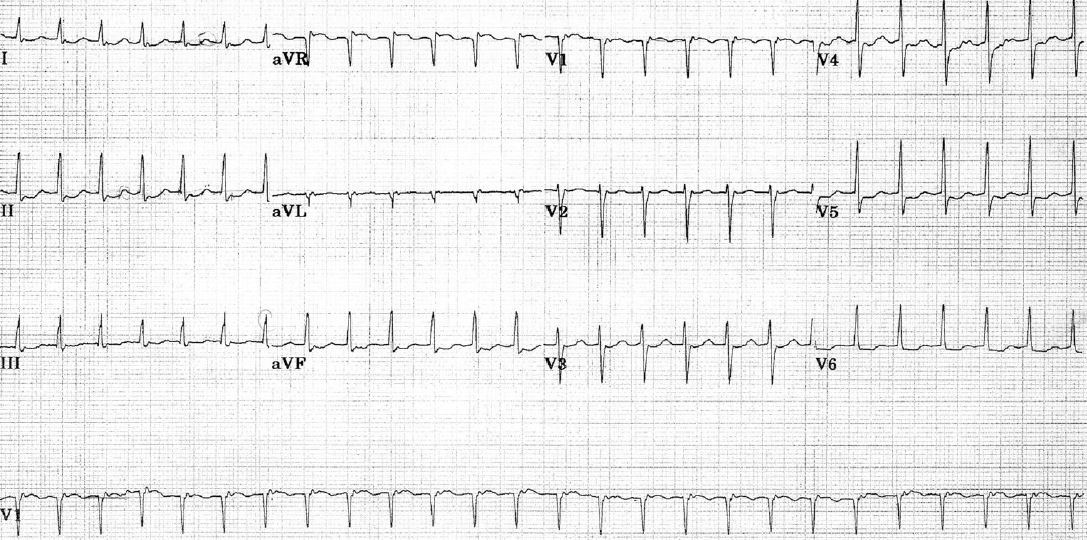

Hypokalemia

Flat T waves + U waves in leads II, III, aVF, V5-6